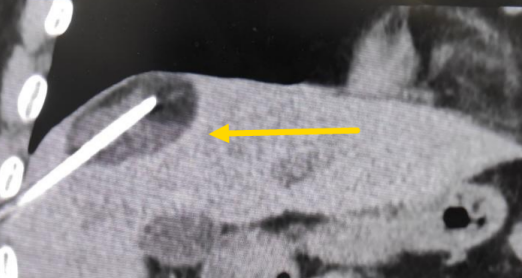

這個患者病變位置刁鉆,穿刺難度大,冷凍消融的難點在于既要不損傷膈肌和肺組織,同時又要盡最大可能完全消融腫瘤。術前陳寶瑩主任、李鐵柱教授、兀云飛醫(yī)生詳細設計進針路徑、布針計劃,術中微創(chuàng)團隊協(xié)調(diào)配合,李鐵柱教授仔細操作,精準到位,順利完成兩個病變的布針,遂啟動治療,先快速降溫到-150多度,再升溫至15?,經(jīng)過兩個循環(huán)反復,即刻觀察到病變完全被冰球覆蓋,同時周圍臟器無損傷,術中患者幾乎沒有疼痛,還和醫(yī)生聊起了天。

術中冰球形成